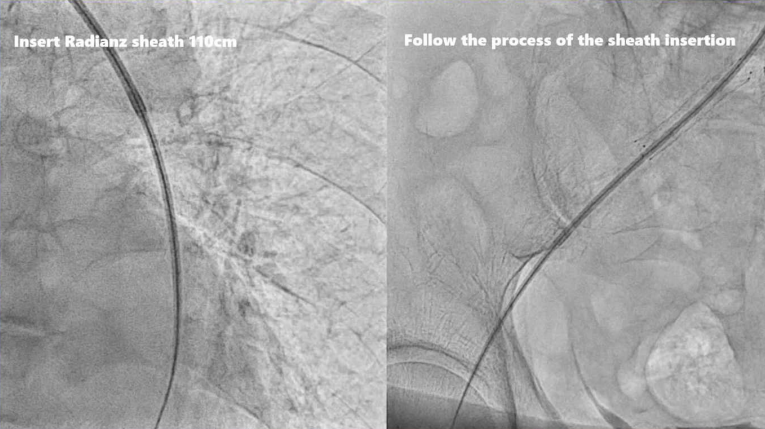

2、在确认鞘管输送顺利的情况下进行,置入110cm Radianz经桡长鞘

动脉长鞘怎么置入桡胜一筹丨原口拓也:经桡动脉入路在下肢动脉疾病腔内治疗中的优势——RADIANZ应用经验_https://www.jmylbn.com_新闻资讯_第23张